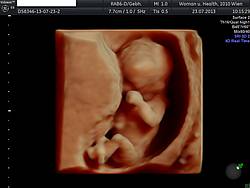

17. bis 22. SSW

Cervixschall: Vaginalultraschall zur Messung der Länge des Gebärmutterhalses. Hier kann ein erhöhtes Frühgeburtsrisiko erkannt und eventuell präventiv behandelt werden.

Bestimmung des kindlichen Wachstums (es werden immer Kopf- und Bauchumfang sowie Oberschenkellänge des Feten gemessen). Kontrolle von Plazentasitz und -auffälligkeiten. Messung von Harn, Blutdruck und Gewicht.